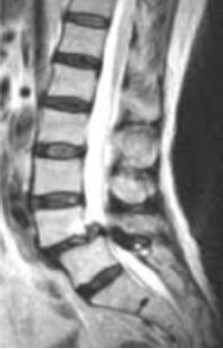

Sobre o diagnóstico evidenciado na ressonância abaixo são feitas três afirmativas.

I. L4-L5 é o nível mais frequentemente acometido por essa patologia.

II. O subtipo ístmico ocorre devido a defeitos nas pars interarticulares, sejam eles fraturas agudas ou crônicas, resultantes de traumas repetitivos.

III. Cirurgia está indicada para os casos em que há mielopatia, radiculopatia ou claudicação neurogênica. Contudo, tratamento conservador pode ser adequado para os casos em que não há bordas escleróticas, mas há sinais de atividade inflamatória nos exames de imagem.

Sobre a veracidade dessas afirmativas, estão CORRETAS